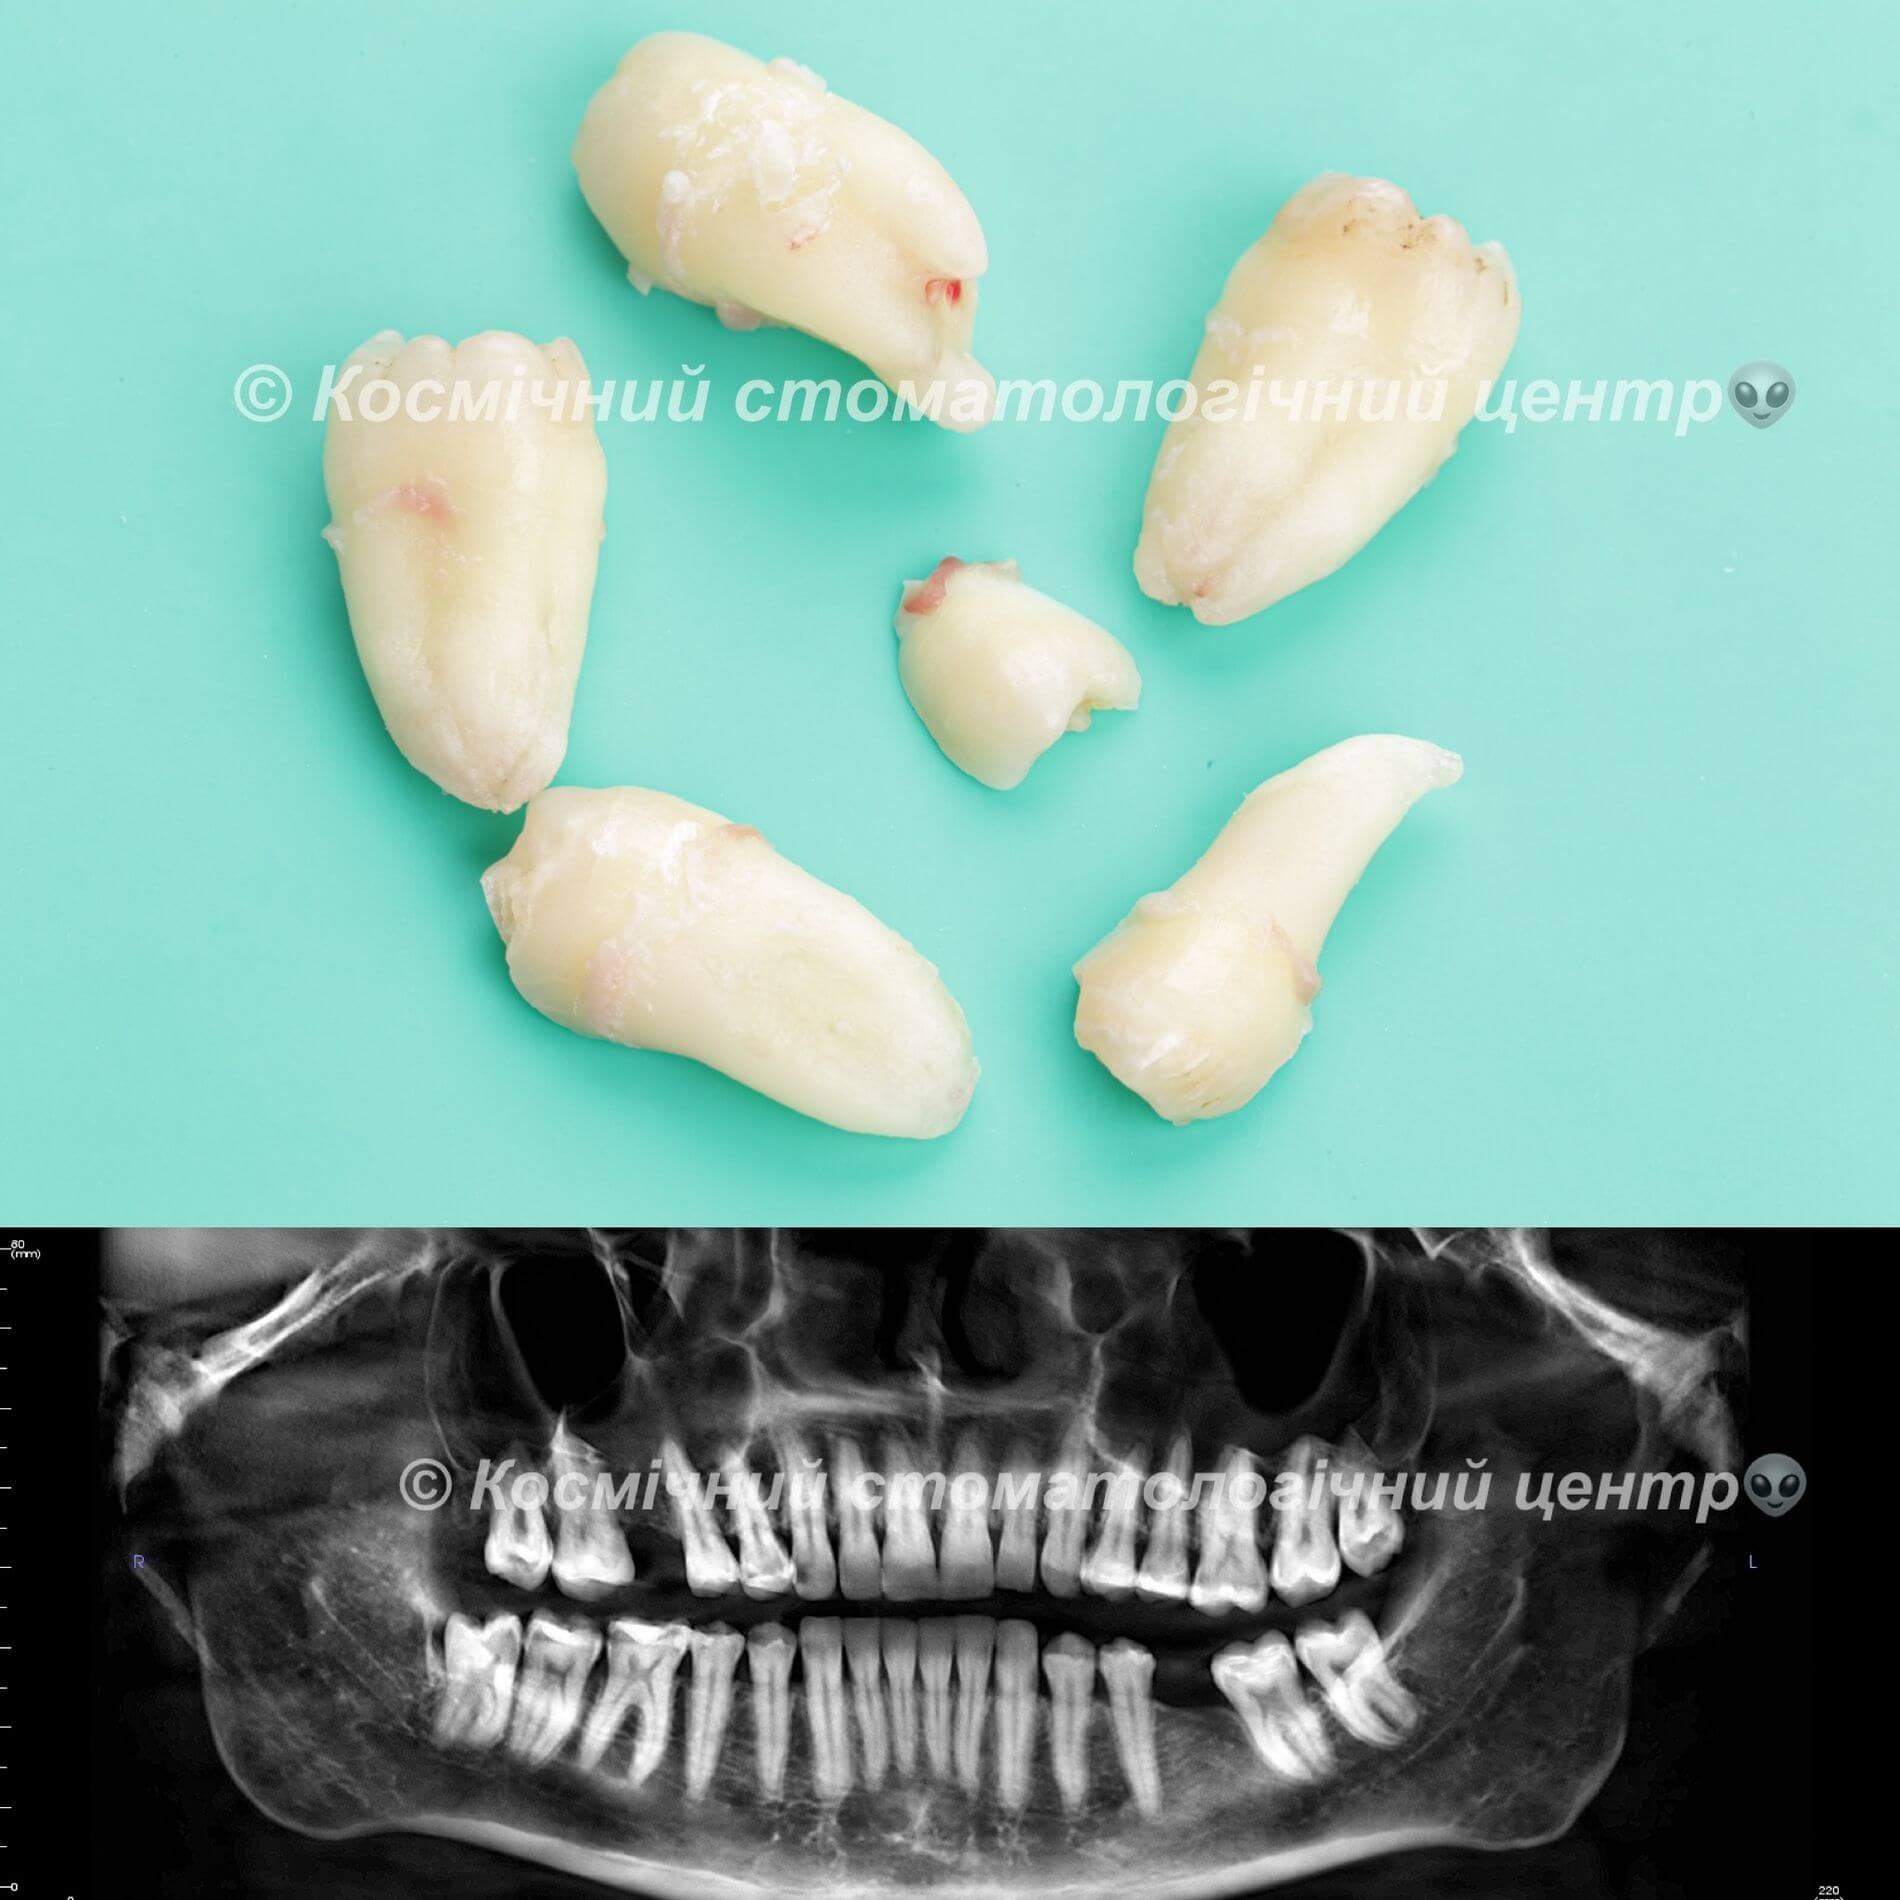

Галерея